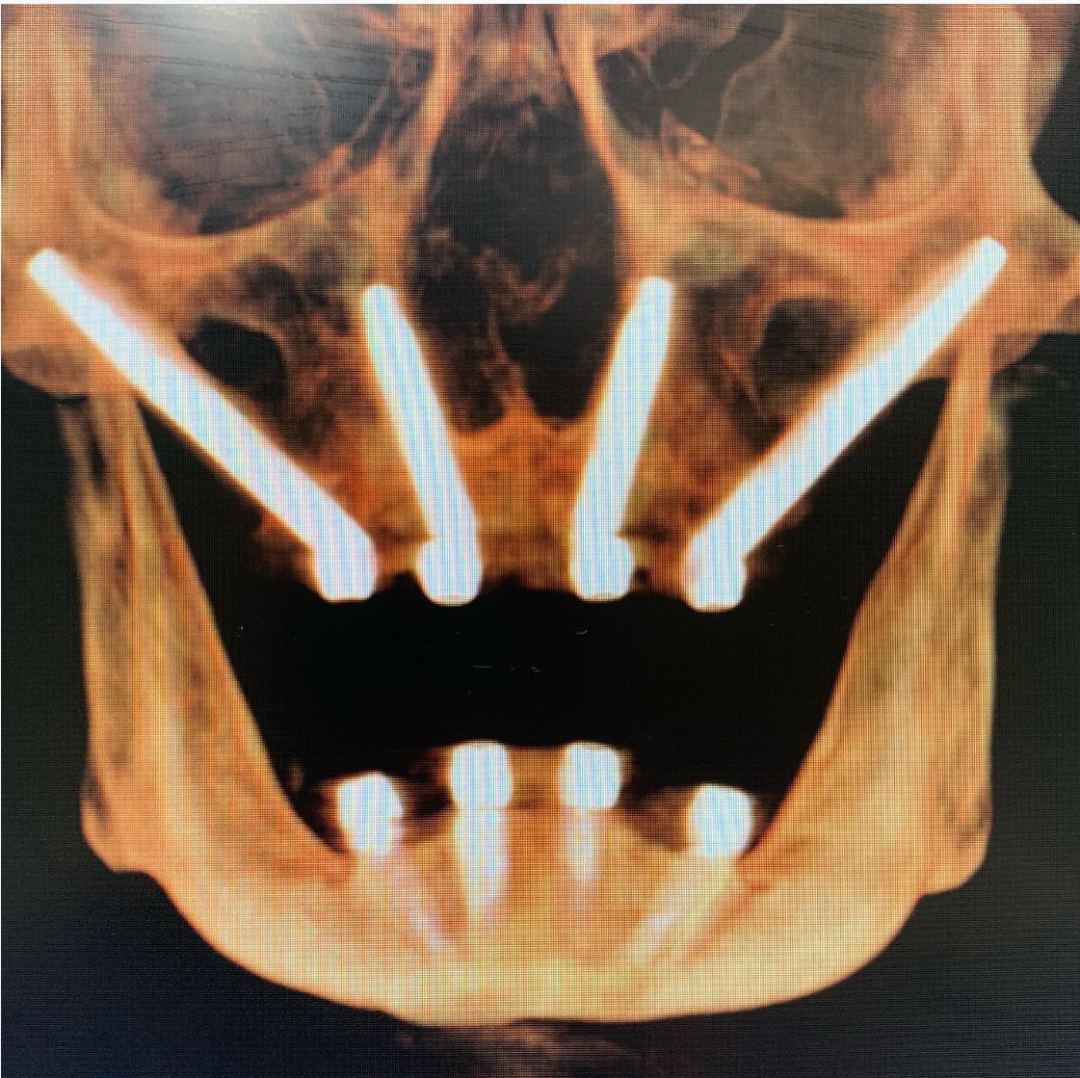

经鼻种植体主要用于替代上颌四颗颧骨种植体(quad zygoma)的植入方案。四联颧骨种植仅适用于鼻下骨量极度匮乏的极端病例。该技术的核心目标是通过在前牙区植入1-2颗经鼻种植体,避免使用4颗颧骨种植体。

尽管经口入路植入鼻骨的方式看似非常规,但其优势显著:相较于四联颧骨种植,该技术不仅能提供更强的骨结合强度,还具有更低的手术风险。由于四颗颧骨种植体常面临空间不足的难题,此时经鼻种植体便展现出独特的临床价值。

经鼻种植体必须由精通远程锚定种植技术(且具备丰富临床经验)的种植专科医师实施。该技术能在确保安全的前提下实现即刻负重。若不符合经鼻种植条件,患者只能选择上颌四联颧骨种植或通过块状骨移植重建前牙区骨量。

真正符合经鼻种植解剖条件的患者极为罕见——多数患者无法满足这一理想植入位点的要求。关键在于鼻泪管(nasal lacrimal duct)与植入区必须保持足够间距。若解剖条件允许,此技术将成为首选方案。